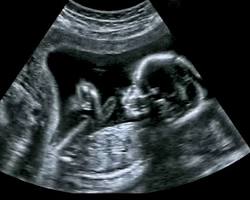

- To monitor pregnancy: Pelvic ultrasounds are routinely used to check on the baby’s growth and development, as well as to assess the mother’s placenta and amniotic fluid.